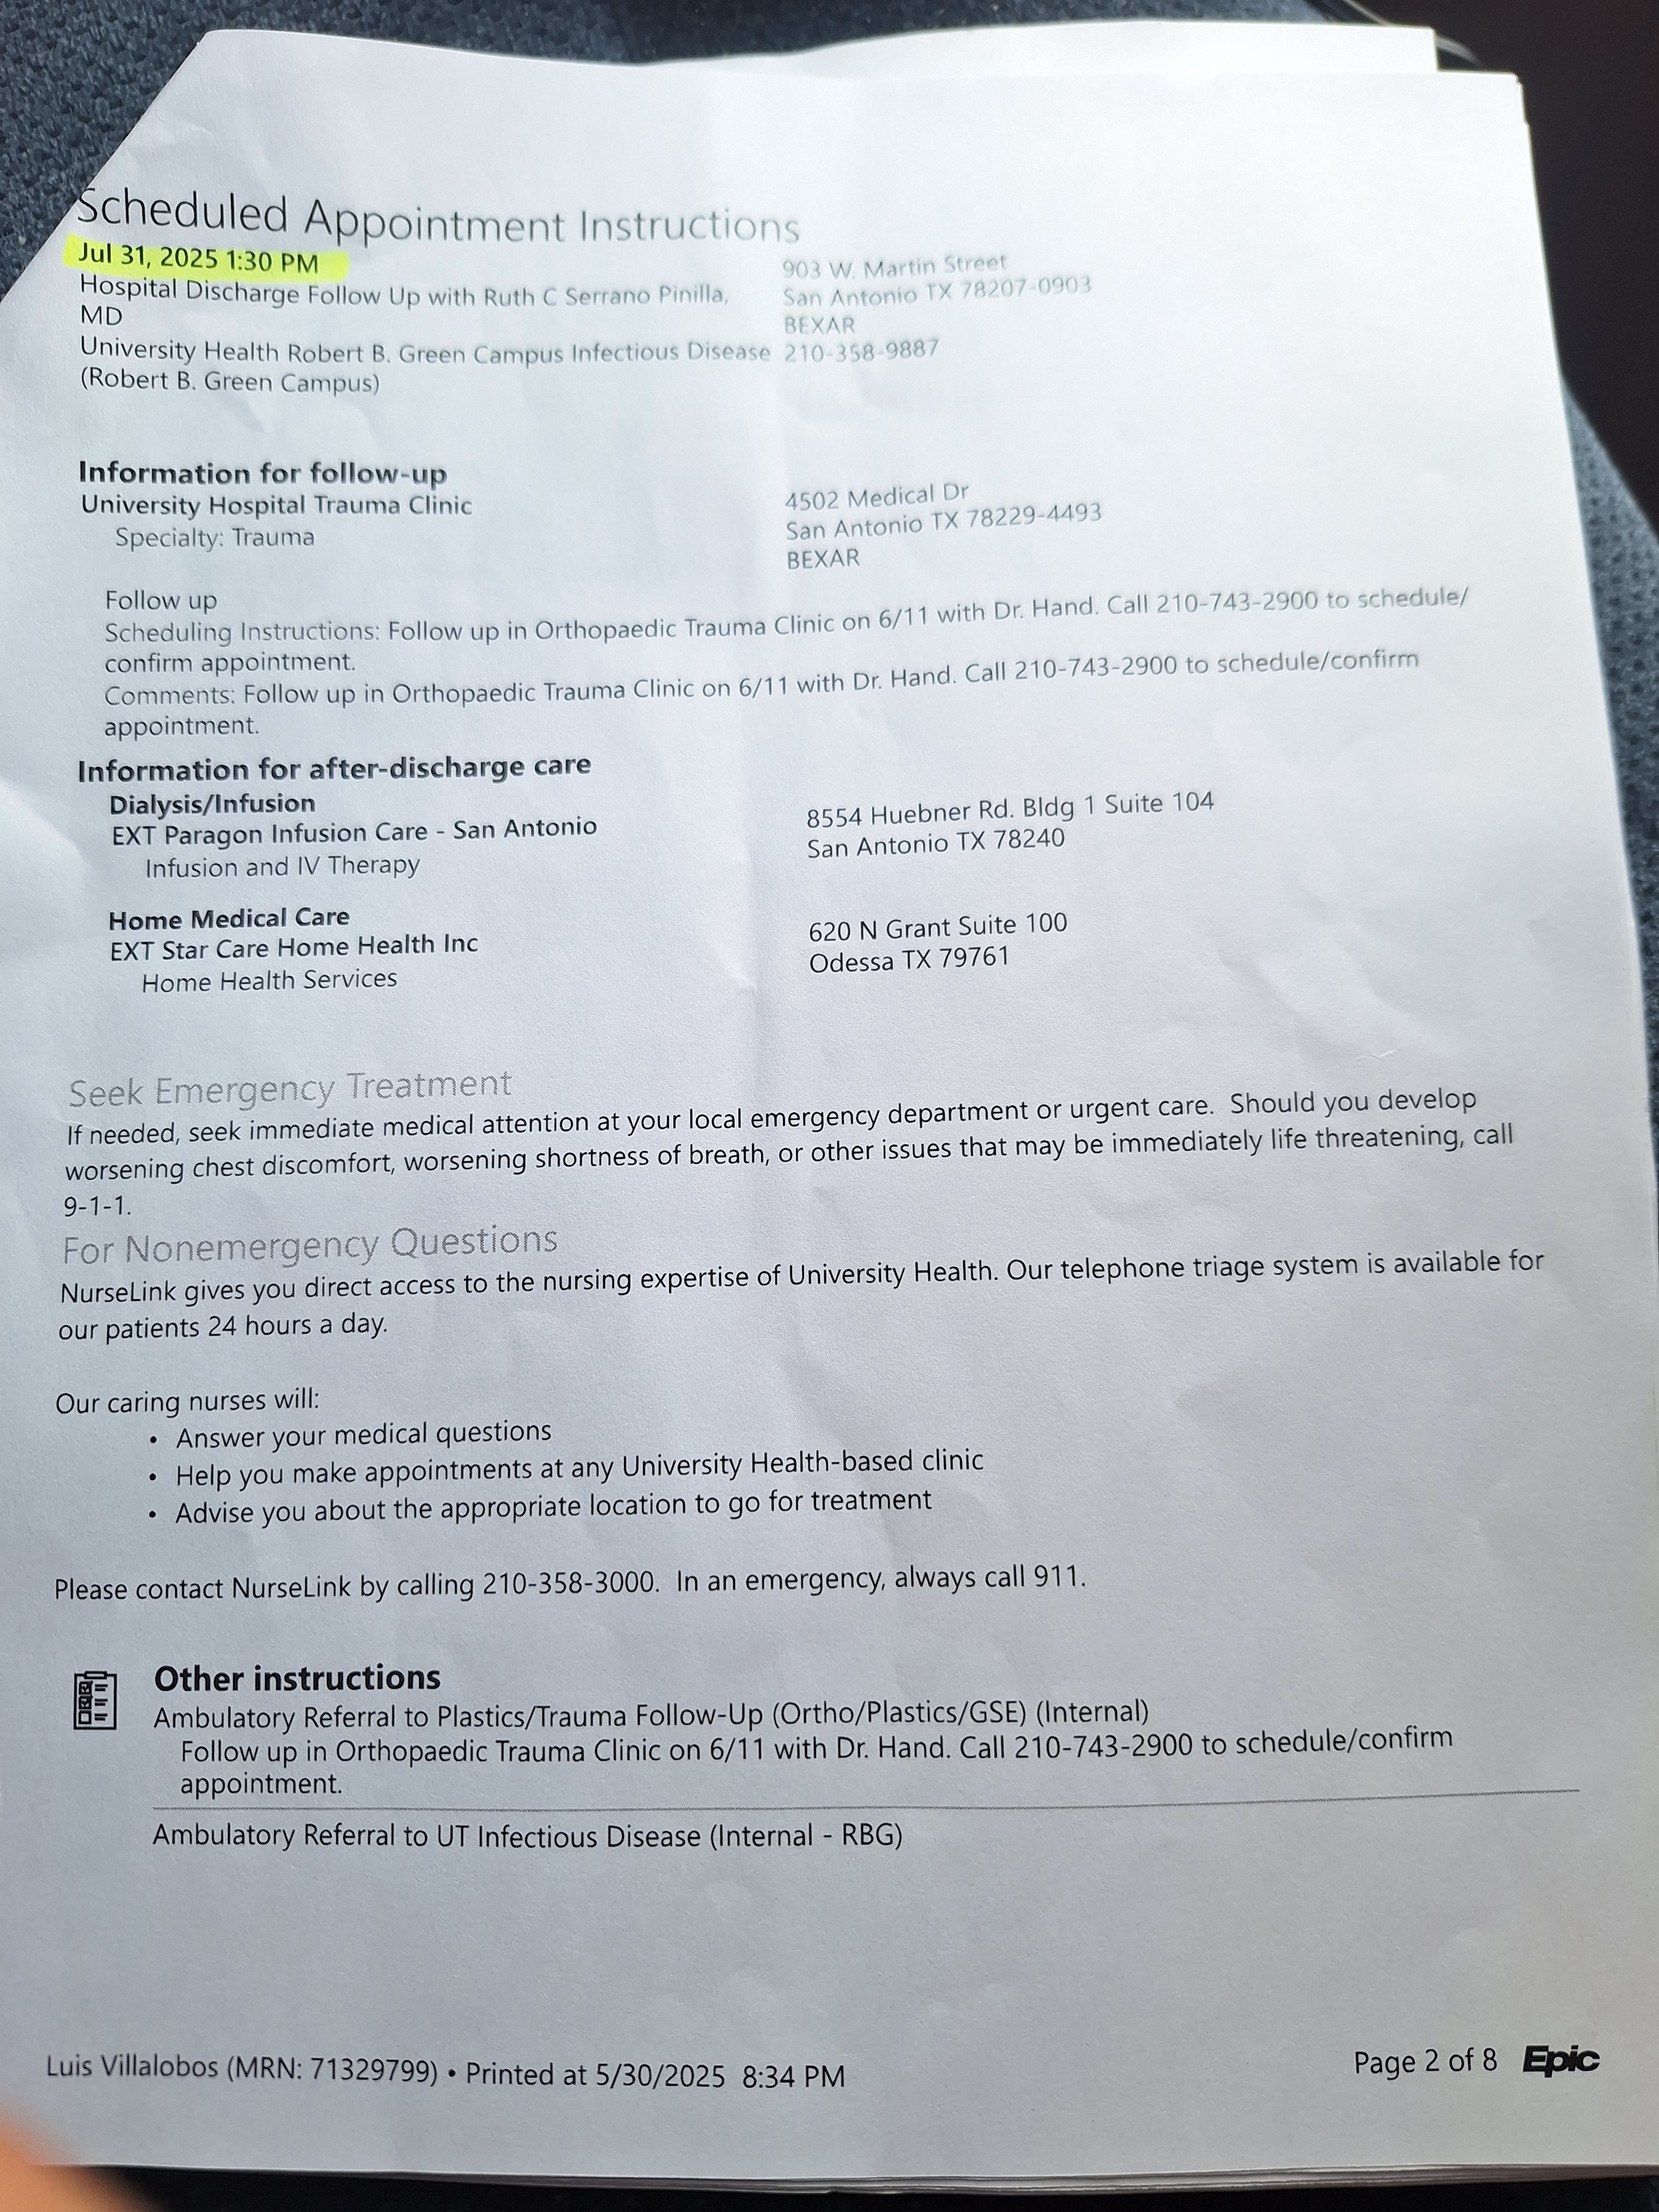

To help you understand the extent of my medical journey, I've included a picture of my discharge paperwork, which reflects the severity and ongoing nature of my condition.

Para ayudarles a comprender la magnitud de mi viaje médico, he incluido una foto de mi informe de alta hospitalaria, que refleja la gravedad y la naturaleza continua de mi condición.